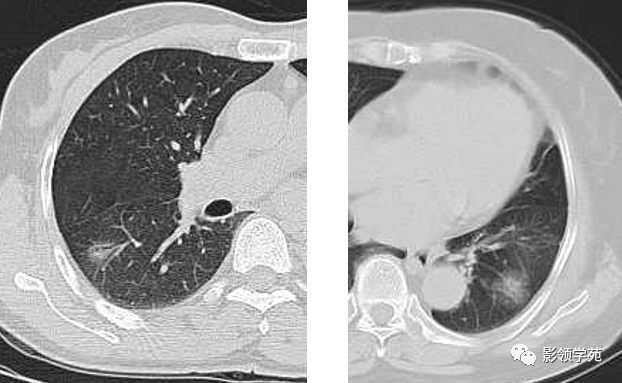

肺大泡

图片尺寸500x532

图片尺寸500x308![【影像读片】影像读片 肺泡细胞癌?结节病?抑或其它 [病例帖]](https://i.ecywang.com/upload/1/img0.baidu.com/it/u=3651163542,2620240397&fm=253&fmt=auto&app=138&f=JPEG?w=500&h=343)